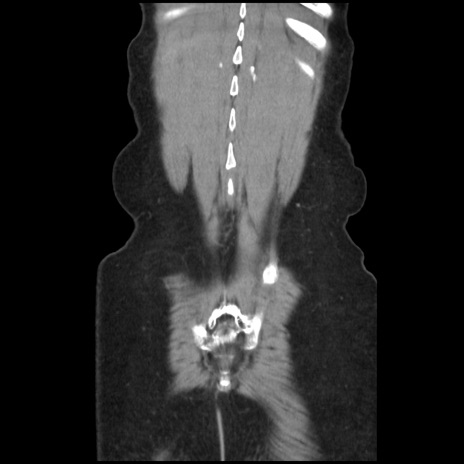

矢状断像